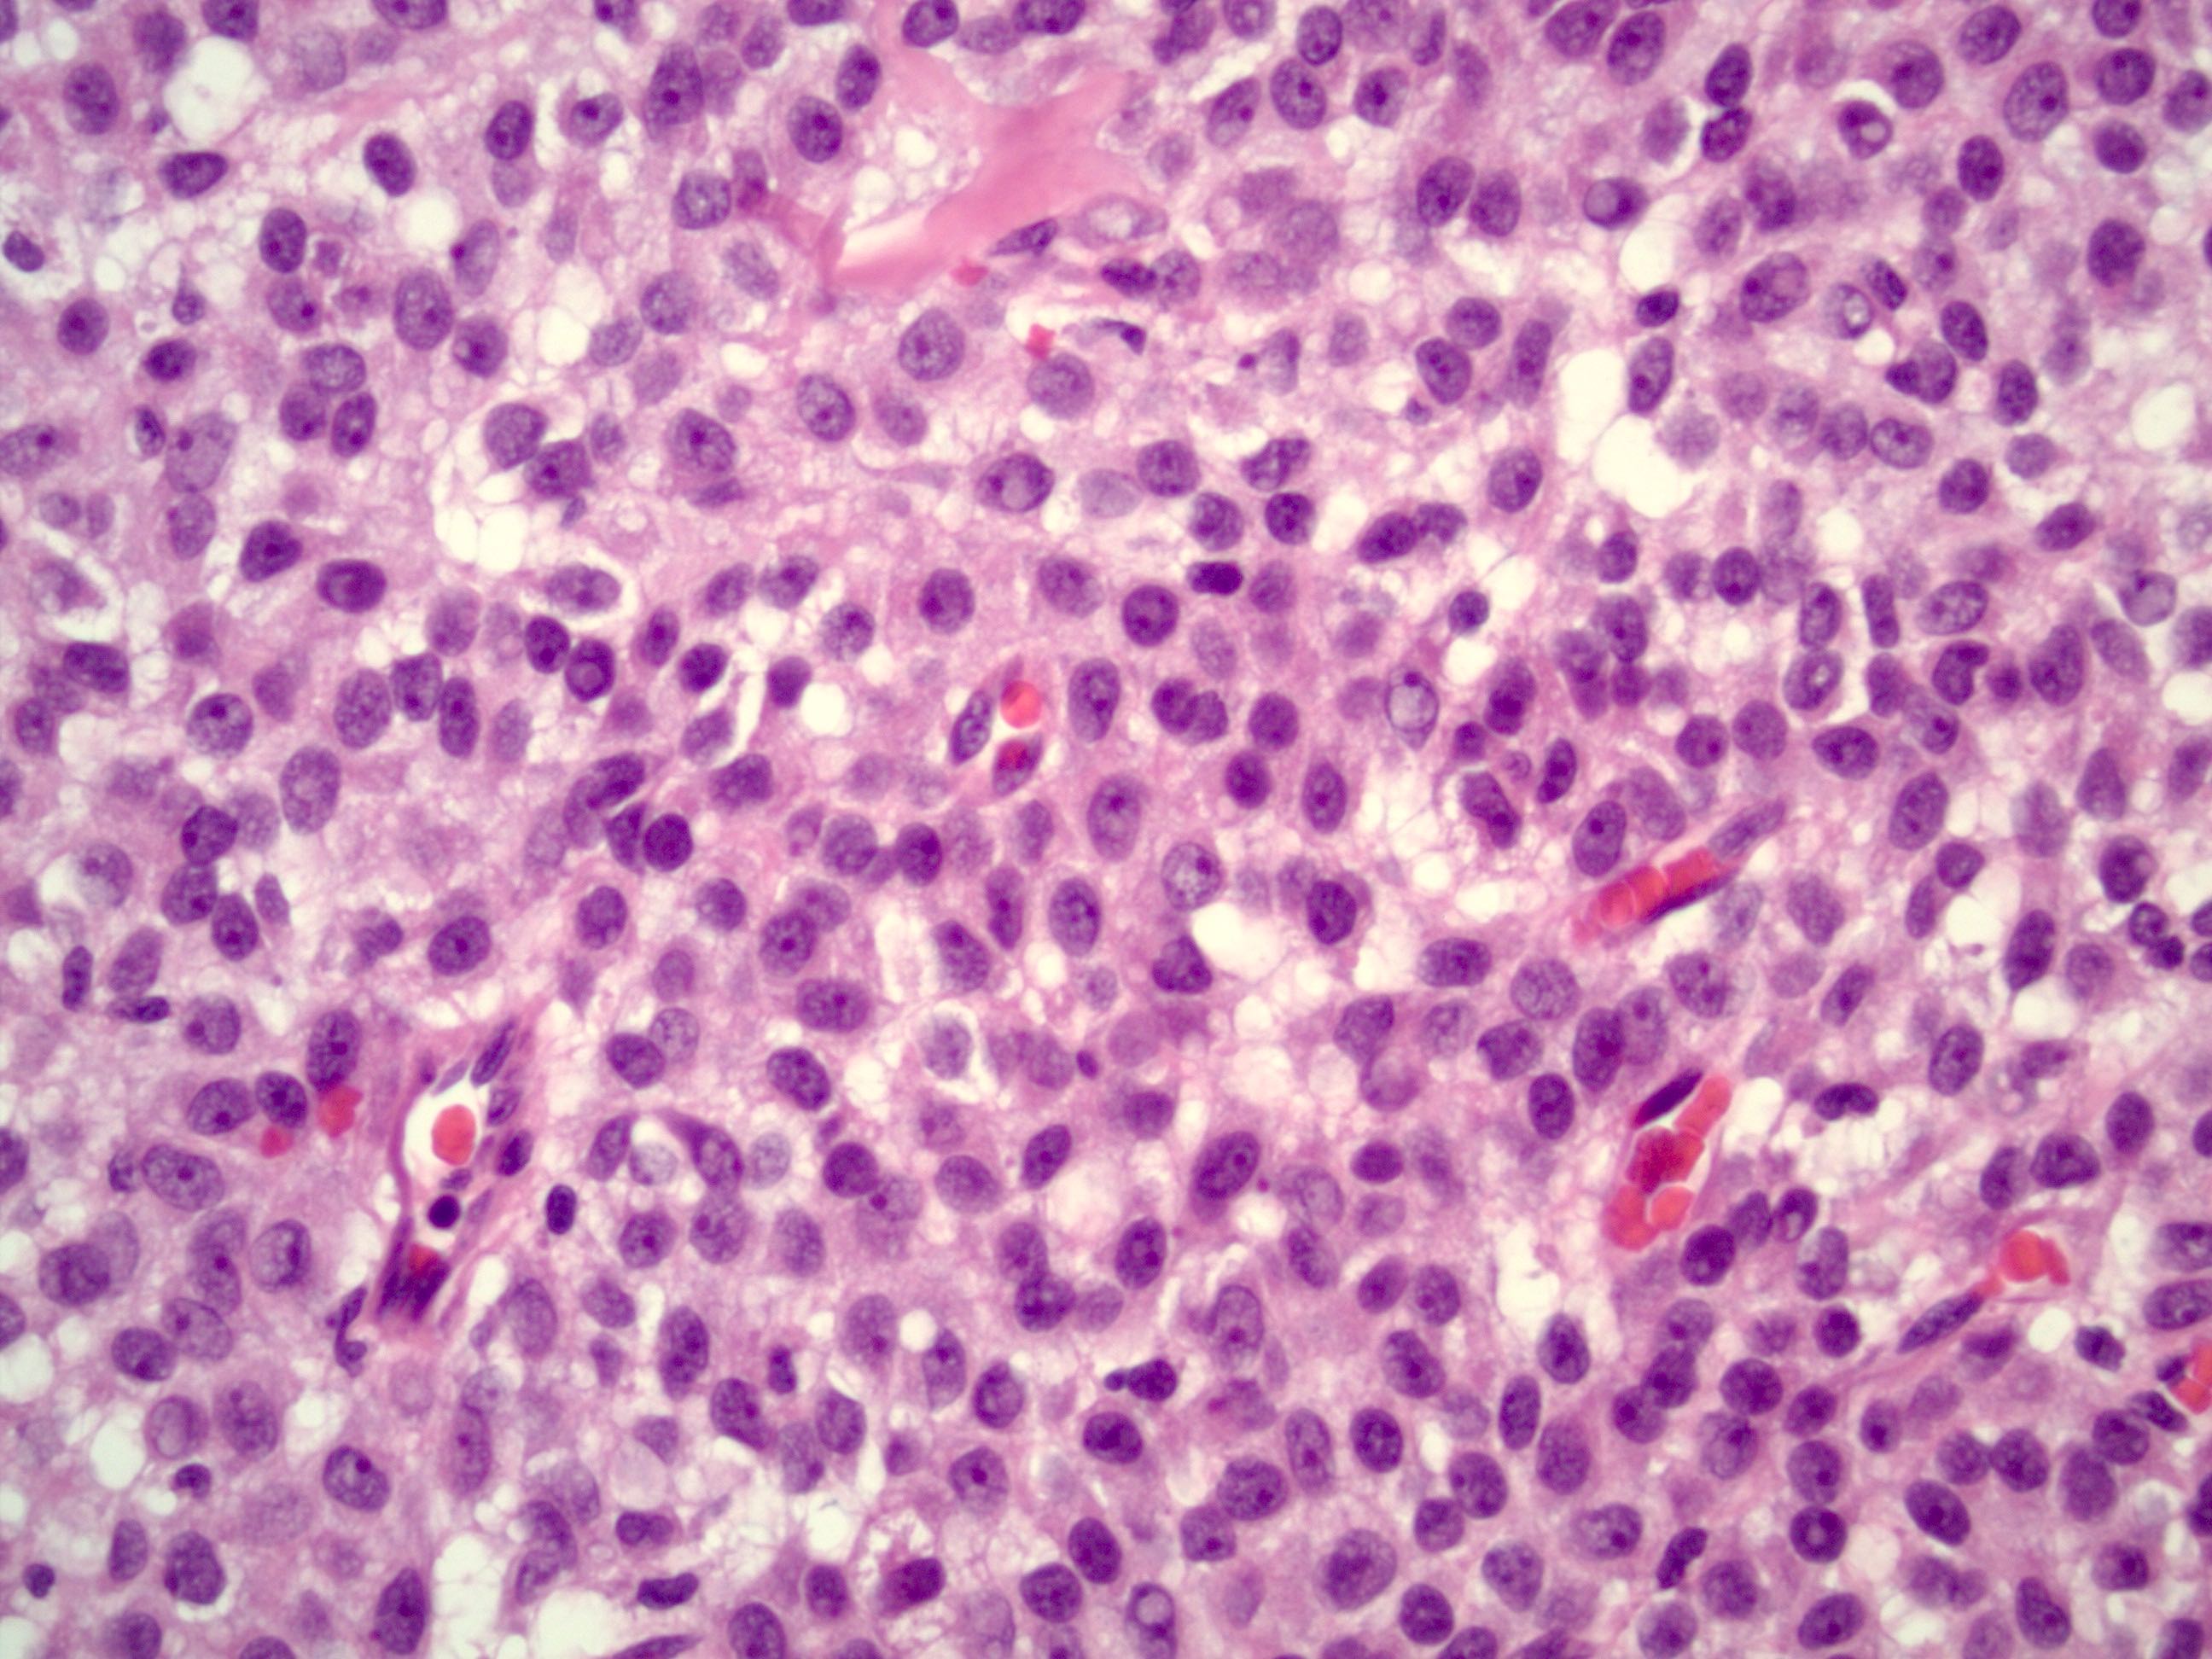

- Small, bland, cuboidal to polygonal cells with scant cytoplasm and pale, uniform angulated and usually grooved nuclei (coffee bean)

- Various patterns, including diffuse (the most common), trabecular and corded, insular, microfollicular (resembling Call-Exner bodies of the Graafian follicles: small follicle-like structures filled with eosinophilic material) and macrofollicular (the least common)

- Usually a mixed growth pattern is seen

- Mitotic activity is usually not brisk (< 3/10 high power fields)

- Stroma is usually hypervascular with variable amounts of fibroblasts and theca cells

Contributed by Shabnam Zarei, M.D. and Sharon Bihlmeyer, M.D.

AFIP images